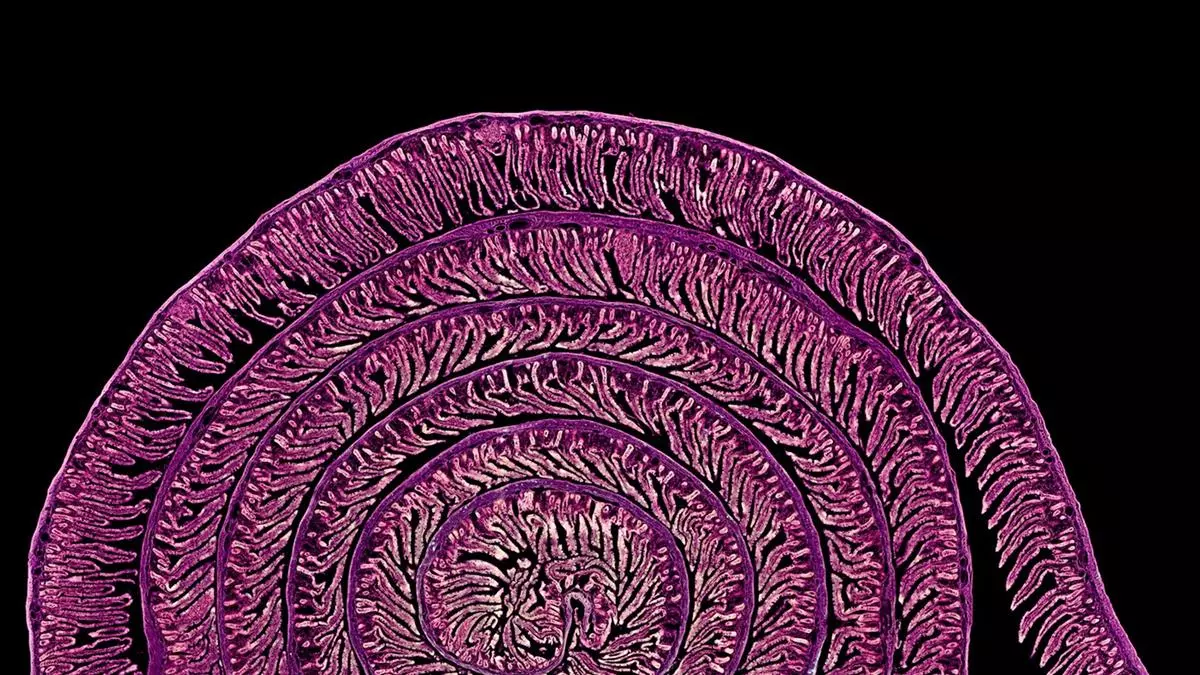

La fotografía científica 'Uzumaki' —espiral en japonés—, realizada por los científicos Daniel García Ovejero y Javier Mazarío Torrijos, del Hospital Nacional de Parapléjicos de Toledo, fue galardonada con el segundo premio en la modalidad Micro de 'FOTCIENCIA21'.

La imagen seleccionada corresponde a una micrografía obtenida a partir de un corte de pocas micras de grosor que abarca 8,5 cm de intestino de rata, captada con un objetivo 10x, en la que se distinguen vellosidades y criptas intestinales dispuestas en una voluta o espiral, semejante a la concha de un caracol.

El intestino es un órgano complejo de analizar al microscopio por su forma tubular y gran longitud. Para abordar este reto, en histología se emplea la disposición de la muestra en "rollo suizo", que consiste en enrollar cuidadosamente el tejido intestinal antes de realizar los cortes finos, generando preparaciones en las que el órgano aparece organizado en espiral.